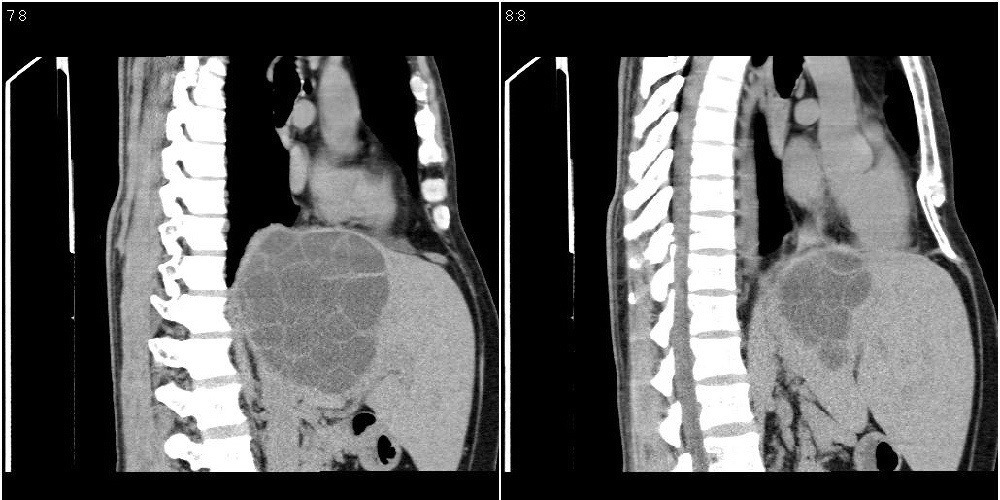

该患者70岁男性,手术后10年,现复查。2008年6月份本人曾经发过一极其类似的病例,只是部位略有差异。

肝脏及右侧胸腔包虫病。

大囊套小囊!肝脏多房性包虫囊肿